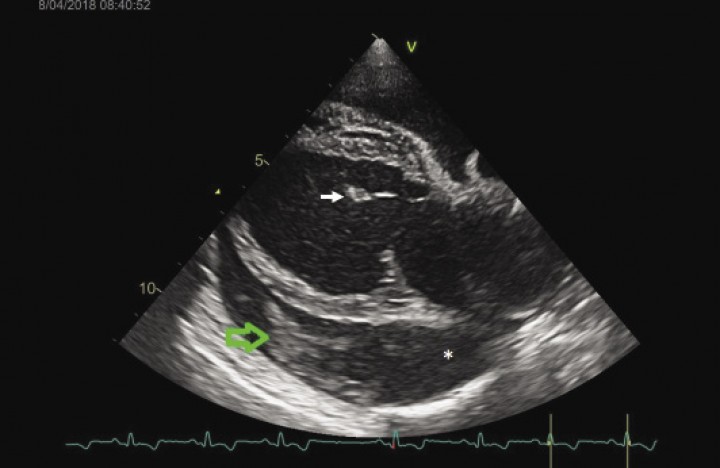

La prueba de elección para valorar las estructuras cardiacas es la ecocardiografía. En el examen ecocardiográfico (Fig. 3) se observó un área hipoecogénica rodeando el corazón, entre el saco pericárdico y las paredes cardiacas, compatible con efusión pericárdica. En el líquido pericárdico se apreció una estructura hiperecogénica, compatible con un coágulo, situada ventralmente al ventrículo y la aurícula izquierda en el eje largo paraesternal derecho. La aurícula y el ventrículo izquierdo se visualizaron muy dilatados y las hojas valvulares de la válvula mitral se observaron muy engrosadas y protruyendo hacia la aurícula izquierda. La aurícula y el ventrículo derecho presentaban un tamaño normal y la pared de la aurícula derecha se colapsaba parcialmente.

<p>Imagen ecocardiográfica: eje largo paraesternal derecho. El asterisco marca el líquido pericárdico anecoico y la flecha verde, el coágulo. La flecha blanca señala la hoja valvular de la válvula mitral.</p>

Imagen ecocardiográfica: eje largo paraesternal derecho. El asterisco marca el líquido pericárdico anecoico y la flecha verde, el coágulo. La flecha blanca señala la hoja valvular de la válvula mitral.